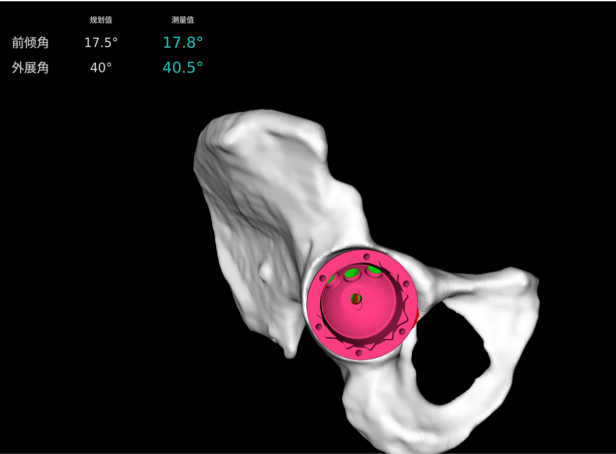

· 個(gè)性化規(guī)劃假體尺寸及安裝角度,預(yù)估安裝效果。

· 融合 CT 和 3D 模型,直觀顯示假體植入效果。

· 制定詳細(xì)植入計(jì)劃,術(shù)前預(yù)演

· 精準(zhǔn)高效執(zhí)行手術(shù)操作,實(shí)時(shí)安裝角度顯示,誤差控制在1°以內(nèi)。